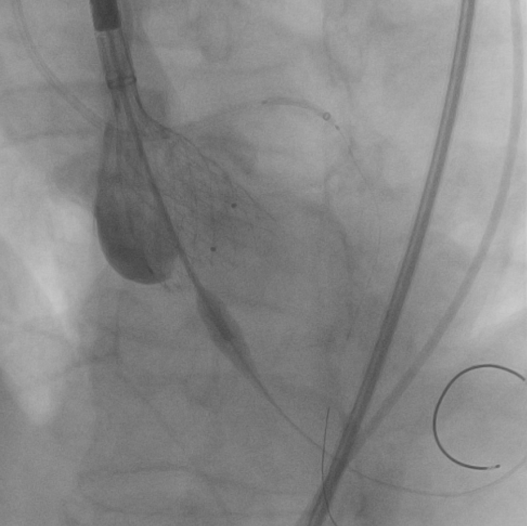

12月31日首都医科大学附属北京同仁医院心血管中心郭彩霞教授团队顺利完成首例TAVR手术。术中22mm球囊预扩冠脉不显影随即进行左冠冠脉烟囱支架保护,植入VenusA Plus可回收L26瓣膜,植入后位置良好,跨瓣压差近乎为零,整个手术一气呵成,手术取得圆满成功,手术后患者状态良好,成功救治82岁高龄患者。体现了心血管中心团队的综合救治能力,标志着在结构性心脏病的微创治疗方面达到国内先进水平。